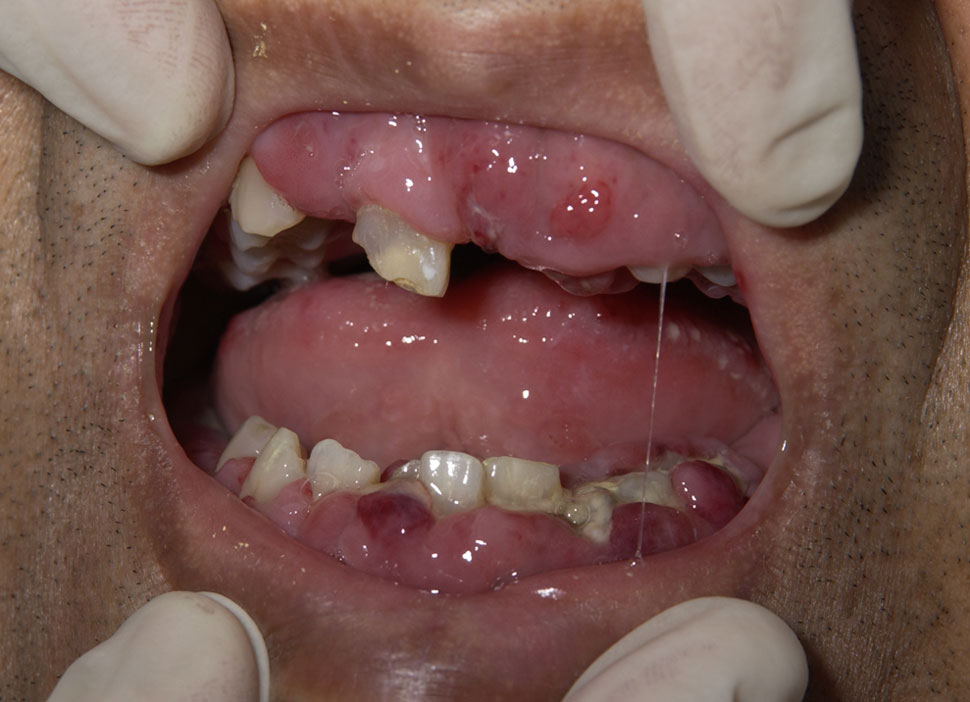

급성 골수성 백혈병 환자 중 일부는 백혈병 세포가 잇몸 조직으로 침윤하여 잇몸이 부어오를 수 있다.[7] 위장관, 호흡기] 등 다른 부위 침범도 가능하지만 흔하지 않다.[8] 치료에 특히 중요한 부위는